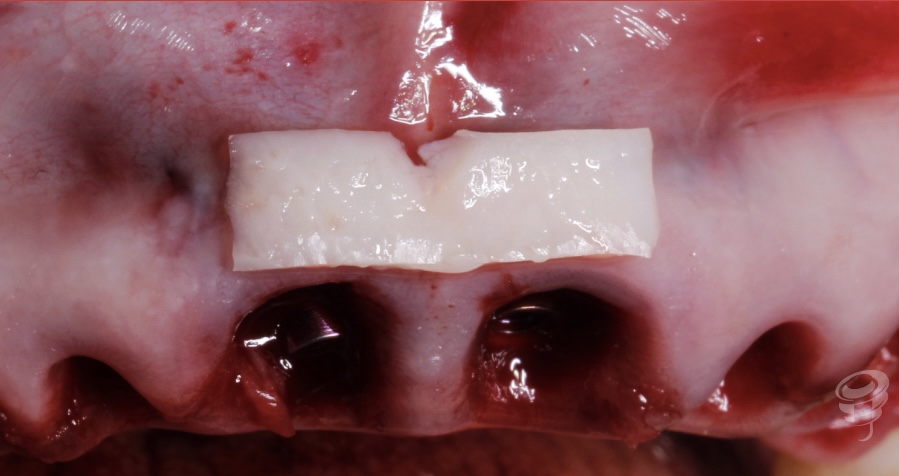

Realizamos extracción de las piezas afectadas periodontalmente. Colocamos los implantes en posiciones, 14, 13, 11, 21 y 23. Simultáneamente un injerto de tejido queratinizado desepitelizado, en zona 11 y 21, para ganar volumen.

Figura 5